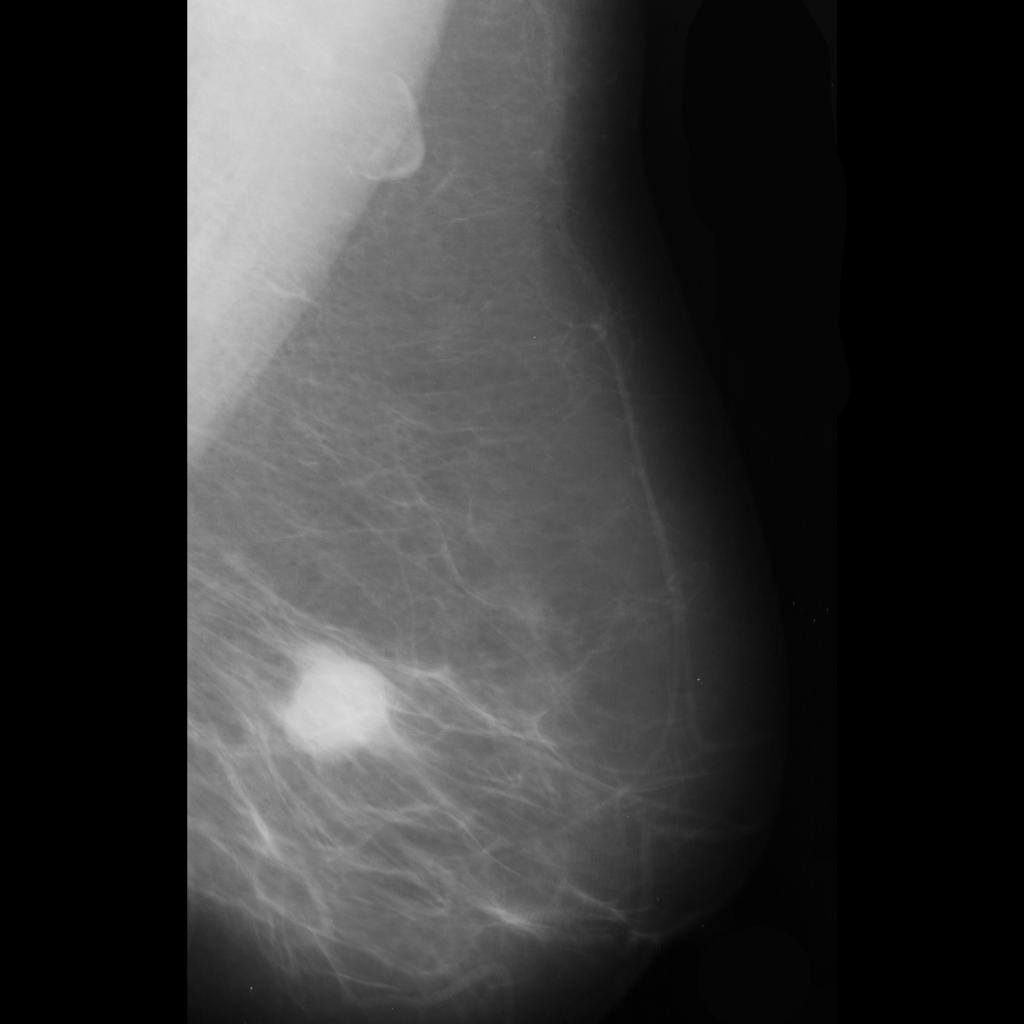

malignant